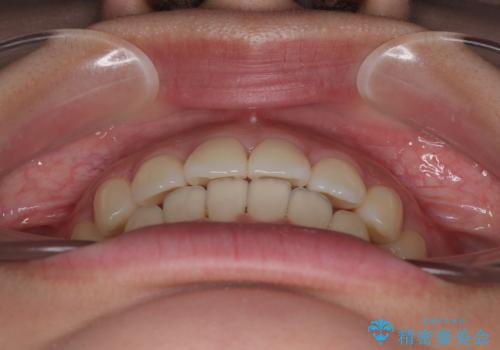

- 上下前歯のデコボコを気にして来院された患者様です。

ワイヤー矯正でもマウスピース矯正でも可能でしたが、短期間で、自身の手を煩わせることなく治療を行いたいとのことで、ワイヤー装置にて矯正治療を行うこととしました。

舌の突出癖により、出っ歯仕上がりとなる可能性がありましたが、舌のトレーニングを頑張っていただき、1年強で終えることができました。